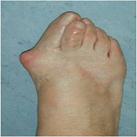

Symptoms include pain in the bump area with or without shoes and occasionally associated discomfort in the ball of the foot (metatarsalgia) and/or lesser toe deformities (Fig 2) such as a hammertoe from direct pressure of the big toe. The diagnosis is confirmed by clinical assessment and x-rays (Fig 3).